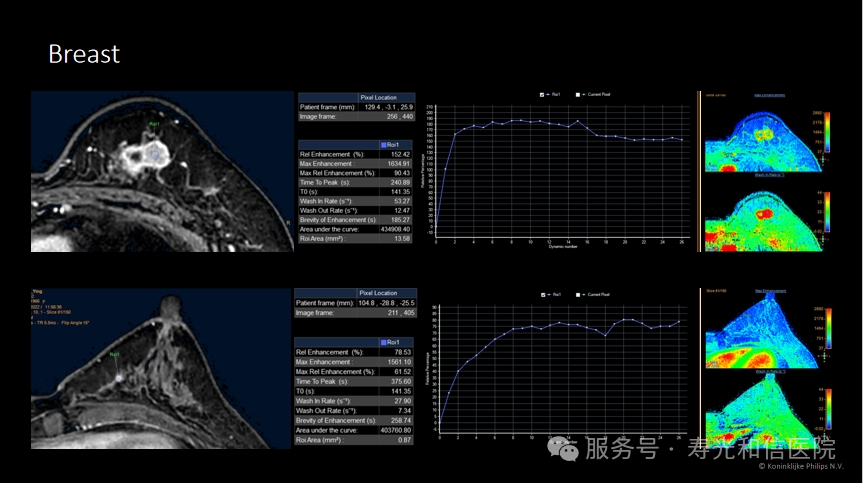

2. 发现早期癌变:MRI对肿瘤的血液供应非常敏感,能捕捉到毫米级的早期癌变或高危病变(如导管原位癌)。

3. 评估肿瘤范围:对于已确诊乳腺癌的患者,MRI能清晰显示肿瘤的实际大小、是否侵犯周围组织,帮助医生制定精准的手术方案。

1. 需要打针:检查前需注射造影剂(增强MRI),以观察肿瘤的血流特点。